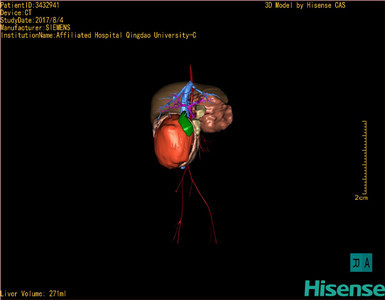

将0.625mm双源薄层CT资料的静脉期和动脉期Dicom格式文件导入海信CAS系统。

通过调节窗宽窗位调整CT序号,对肿瘤,肝实质,胆囊,下腔静脉,肿瘤,肝动脉、门静脉及肝静脉等进行三维重建;系统自动计算肿瘤体积和肝脏体积。

模拟手术操作,自动计算切除肿瘤体积。肝脏体积为271ml,通过术前模拟手术,精准判断手术可行性。

术前三维重建:

重建图片